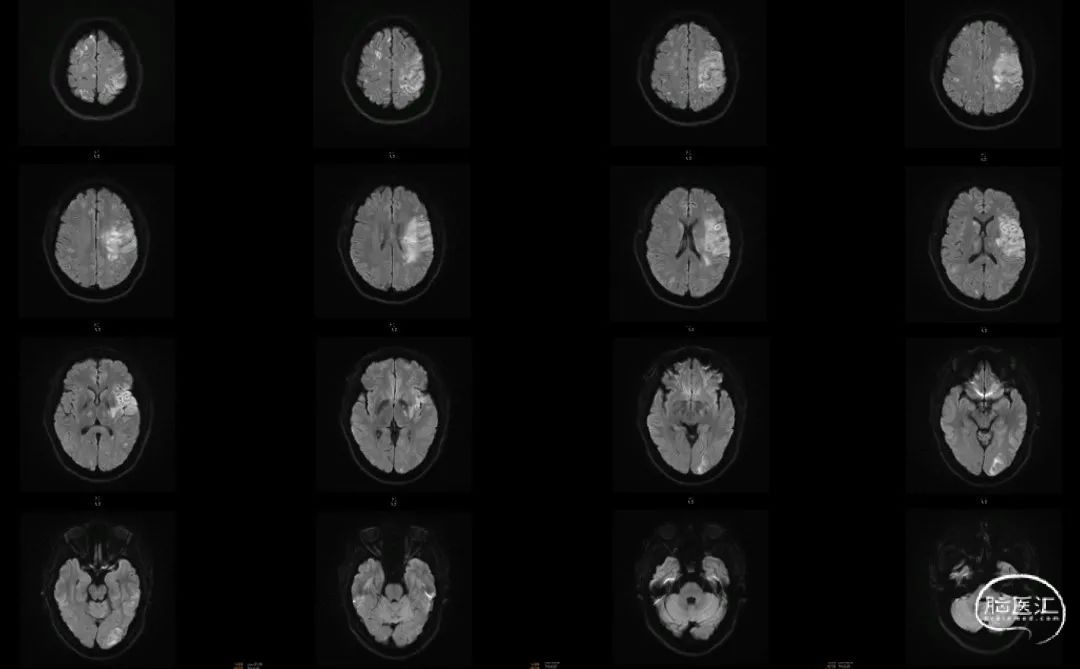

术前CTA+CTP:术前CTA可见左侧后交通动脉开放,左侧颈内动脉末端、大脑前动脉和大脑中动脉显影,左侧颈内动脉C6近端、大脑中动脉M1远端未显影。左侧颈内动脉区域CBF下降,CBV大致正常,MTT、TTP延长。

左右滑动查看更多

术后1周MRI: